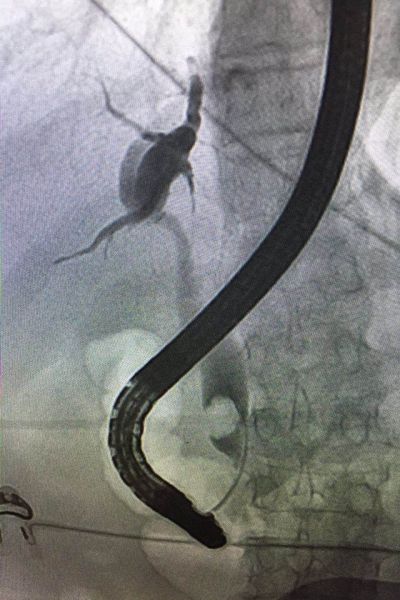

患者是一位80 岁的老年女性,因“腹痛、发热、黄疸2天”来我院求治,入院时体温39℃,血压80/40mmHg,胆红素282mmol/L,腹部CT提示胆总管下段结石,诊断胆总管结石并急性化脓性胆管炎明确。按照传统治疗方案,患者需要行外科手术。但此时手术风险极高,且术后患者需较长时间保留T管引流。有鉴于此,科主任李学锋、李凯组织消化科田家晖副主任医师、向仍运主治医师以及肝胆外科专家进行会诊,最终决定,予以患者施行急诊鼻胆管引流术。经过有序的术前准备,在外科的通力配合下,在李学锋主任和李凯主任的指导下,向仍运主治医师通过十二指肠镜对胆总管进行插管,插管成功后首先抽吸出脓液减压,再对胆总管进行造影显示出结石的位置、形态及大小,最后在结石以上胆管置入鼻胆管引流。手术过程非常顺利,历时不到40分钟,术后患者疼痛即消失,血压、白细胞、胆红素很快恢复至正常。

ERCP即逆行胰胆管造影,用十二指肠镜在X线透视下对胆管、胰管进行显影,并对病变进行相应治疗,属于四级手术。特别适用于胆总管结石、急性化脓性胆管炎、梗阻性黄疸患者。该操作无需麻醉,痛苦小(相当于做胃镜)。